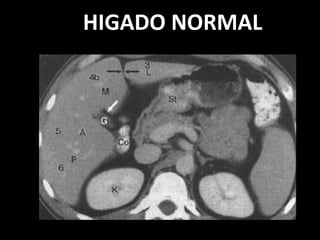

HIGADO NORMAL

Valoración básica hepática

– Forma: contornos, distribución volumétrica

– Tamaño:

• Distribución volumétrica

– Longitudes

– Ángulos

– Ecogenicidad:

• Normal:

– Homogénea, ecos finos

• Hipoecoica respecto al bazo

• Hiper – Isoecoico respecto a la corteza renal